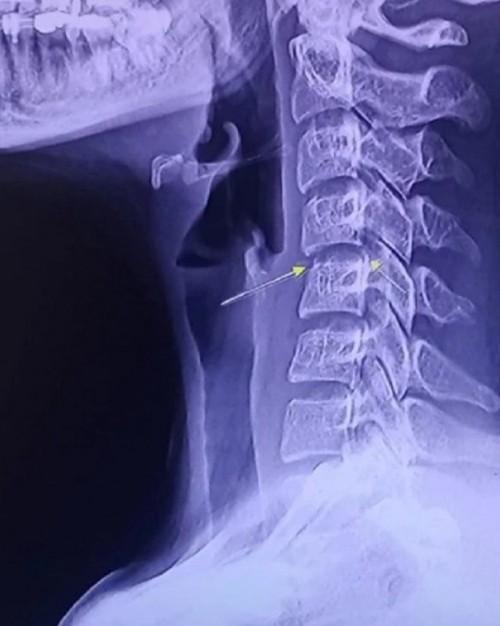

Các trang tin ở Thái Lan cảnh báo, cổ được coi là “điểm yếu” của cơ thể. Việc massage mạnh ở vùng này có thể làm tổn thương tủy sống hoặc các mạch máu đưa máu lên não.

Bác sĩ thần kinh Thiravat Hemachudha người Thái Lan viết, việc vặn cổ hoặc massage cột sống ở vùng cổ có thể gây liệt. 177 bác sĩ thần kinh ở Mỹ báo cáo đã có những bệnh nhân bị liệt do nhồi máu não sau khi được nắn chỉnh cột sống cổ, trong đó có những bệnh nhân chỉ hơn 20 tuổi.

Một bệnh nhân bị liệt nửa người phải và phải nhập viện một tháng do cứ vặn cổ 3 lần/ngày. Bác sĩ Thiravat nhấn mạnh, người dân không nên thực hiện động tác vặn cổ vì có thể ảnh hưởng đến thị lực và sự cân bằng của cơ thể.